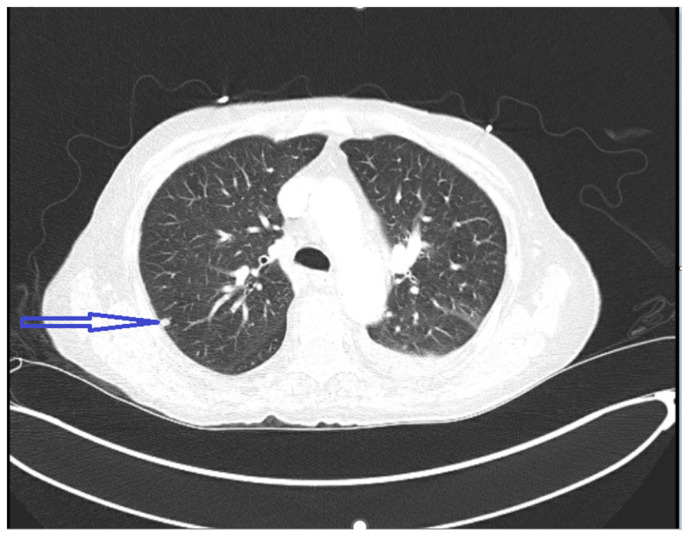

Pancreatic carcinoma has remained one of the leading causes of cancer-related mortality worldwide. Cancer originating in the head of pancreas is often detected early in the disease due to biliary obstruction resulting in jaundice. In contrast, cancer of the pancreatic body and tail remains indolent, presenting late with significantly increased tumor burden and distant metastasis. Unfortunately, a single laboratory screening study is neither sensitive nor specific for early detection of pancreatic cancer. In this report, we present a patient with longstanding diabetes incidentally detected to have pancreatic tail carcinoma while presenting with pulmonary embolism, emphasizing the need for pancreatic cancer screening studies in population with longstanding diabetes.